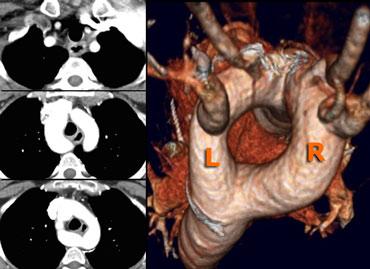

On the left axial images and posterior view of volume rendered reconstruction.

Describe the findings and then continue.

The findings are:

- four vessel sign

- double arch

- right arch higher and larger

- esophagus and trachea are completely encircled

The narrowing of the trachea is seen on the axial images, but better appreciated on the MPR and Volume Rendered image.

On the left preoperative and postoperative MDCT studies of a 2-month-old female infant with double aortic arch presenting with stridor and repeated apnea.

The smaller left arch is partially resected.